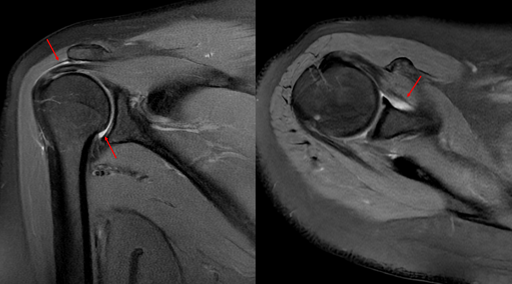

Quy trình thực hiện chụp MRI khớp vai diễn ra thế nào?

Khớp vai là khớp quan trọng trong việc hỗ trợ các vận động của cơ thể ở vùng vai và cánh tay. Do tính chất phải hoạt động liên tục và nhiều, khớp vai rất dễ bị tổn thương. Các tổn thương tại khớp vai được phát hiện chính xác nhất nhờ kỹ thuật chụp MRI khớp vai. Vậy hãy cùng Medlatec tìm hiểu xem...